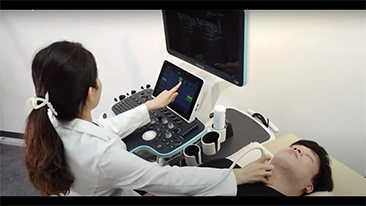

Covid-19 - ?nsanlar ve cihazlar i?in test zaman?

KoronavirĂŒs nedeniyle, hastaneler ve sa?l?k personelleri, akut ortamlarda sosyal mesafe, ki?isel koruyucu ekipmanlar?n (KKD) s?k? bir ?ekilde kullan?m?, el y?kama ve ekipmanlar?n her gĂŒn dezenfeksiyonunu i?eren yeni ?al??ma uygulamalar? geli?tirdi. ?zellikle ko?u?lar ve ameliyathanelerin birka? kata yay?ld??? ve ?zel cihazlara eri?imin ?ok ?nemli oldu?u durumlarda, bak?m noktas?nda, ta??nabilir, yĂŒksek dĂŒzeyde mobil ve ?ok y?nlĂŒ ekipmanlar ?n plana ??kt?.